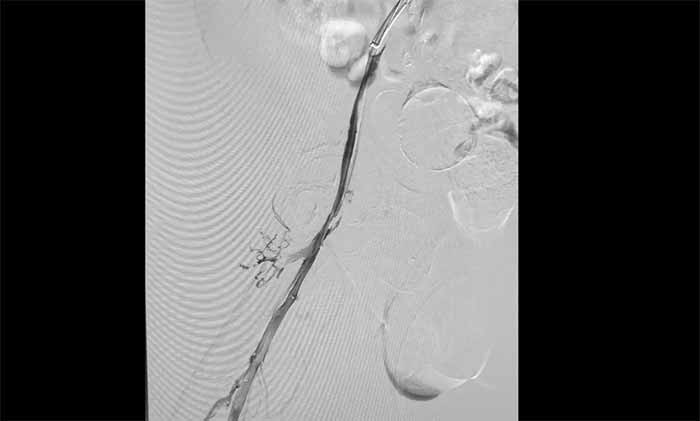

席刚明教授与脑血管病一科4A病区副主任王贵平博士分析指出,下肢深静脉血栓一旦脱落,可随血流引发肺栓塞,危及生命。考虑到患者血栓形成时间较长、抗凝效果不佳,团队决定行介入手术治疗。术后造影显示血栓基本消失,下肢静脉恢复通畅,患者右下肢肿胀明显缓解。

▲ 取出大量血栓